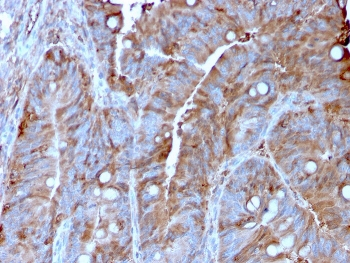

IHC staining of FFPE human colon carcinoma with MerTK antibody (clone TPKR-1). HIER: boil tissue sections in pH9 10mM Tris with 1mM EDTA for 10-20 min and allow to cool before testing.